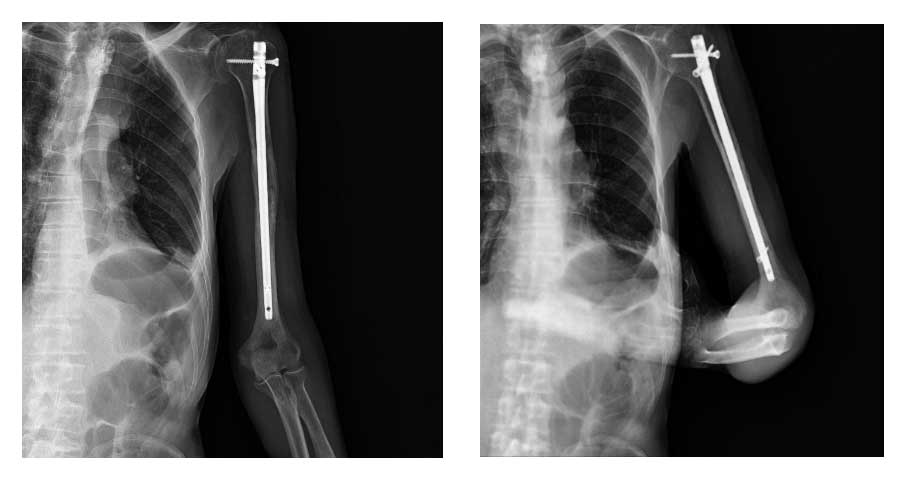

Sol kol kemiği (humerus) metastazına bağlı kırık nedeniyle kapalı çivileme işlemi başarıyla uygulandı.

Ameliyat Sonrası: Röntgende sol humerus kemiği içinde intramedüller çivi görülmekte.